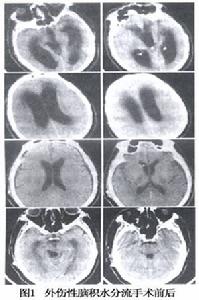

圖1 外傷性腦積水手術方法:局麻或全麻下施術,病人仰臥頭偏向左側,右肩稍抬高使頸部側方伸平。先於右顳後份(外耳道後方及上方各4cm處)行顱骨鑽孔,用腦針垂直穿刺深入3~4cm即達腦室三角區,證實有腦脊液流出後勿過多排放,隨即將分流管的腦室端,按腦針的方向和深度插入腦室,再將單向閥門固定在骨孔稍下方,然後經頭皮帽狀腱膜下層自耳後直至頸側皮下作一隧道,並將分流管的腹腔端導入與閥門出口相接,隨即縫合頭皮切口。分流管遠端繼續經頸部,胸部皮下潛行至右下腹。然後作闌尾炎麥氏切口,剪開腹膜後用環鉗將分流管末端沿盆腔右側壁小心送入直腸膀胱隱窩或子宮直腸隱窩。術畢如常縫合腹壁切口及分段皮膚切口,不放引流 術後投予抗生素預防感染 每天按壓閥門2~3次,以避免單向閥門分流裝置發生阻塞。

預後:

手術後神經症狀一般會有所改善,頭痛消失,精神較為活潑,Zander報導31例外傷性腦積水行腦室至心房分流術後,48%可恢復工作或生活自理 26%無改善,另外26%死亡。